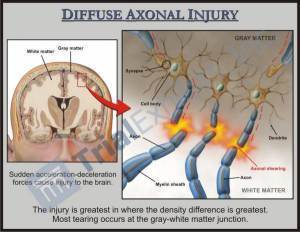

1. “Despite years of research into traumatic brain injury (TBI), the tests currently available to neurologists, emergency physicians, and other experts can’t reliably identify who has sustained a TBI after a blow to the head, and who has not.” [emphasis is mine]

2. “Damage to neurons occurring after a mild to moderate TBI–called axonal injury–is not revealed on these [CT] scans.” [emphasis is mine]

The image I found, below, is generated by one of the latest diagnostic tools, Diffuse Tensor Imaging, or DTI (see #6, below).

image from trialexhibitsinc.com, “Diffuse Axonal Injury (TBI)”

3. “‘Some studies indicate that having had even a “mild” TBI in early or midlife may increase the risk for dementia in late life, probably at least twofold.’” states Ramon Diaz-Arrastia, M.D., Ph.D., Fellow of the AAN [American Academy of Neurology], director of clinical research at the Center for Neuroscience and Regenerative Medicine at the uniformed services University of the Health Sciences in Bethesda, MD. [emphasis is mine]

4. Even a mild to moderate TBI causes an Axonal Injury = one that disrupts the brain’s structure and chemistry on a cellular level. [emphasis is mine]

6. There is a new type of MRI called Diffusion Tensor Imaging (DTI) that is promising for seeing the neurological damage caused by TBIs in ways no other diagnostics are currently able to do. This will also aid in detecting where an injured person is in their recovery.

image from http://www.adlergiersch.com, “Advances in Neuroimaging in Detecting Brain Abnormality in ‘Mild’ Traumatic Brain Injury”